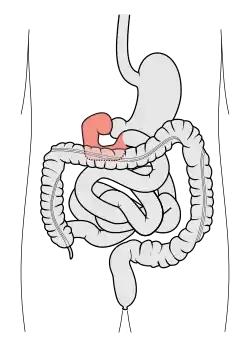

Image of the gastrointestinal tract, with the duodenum highlighted. | |